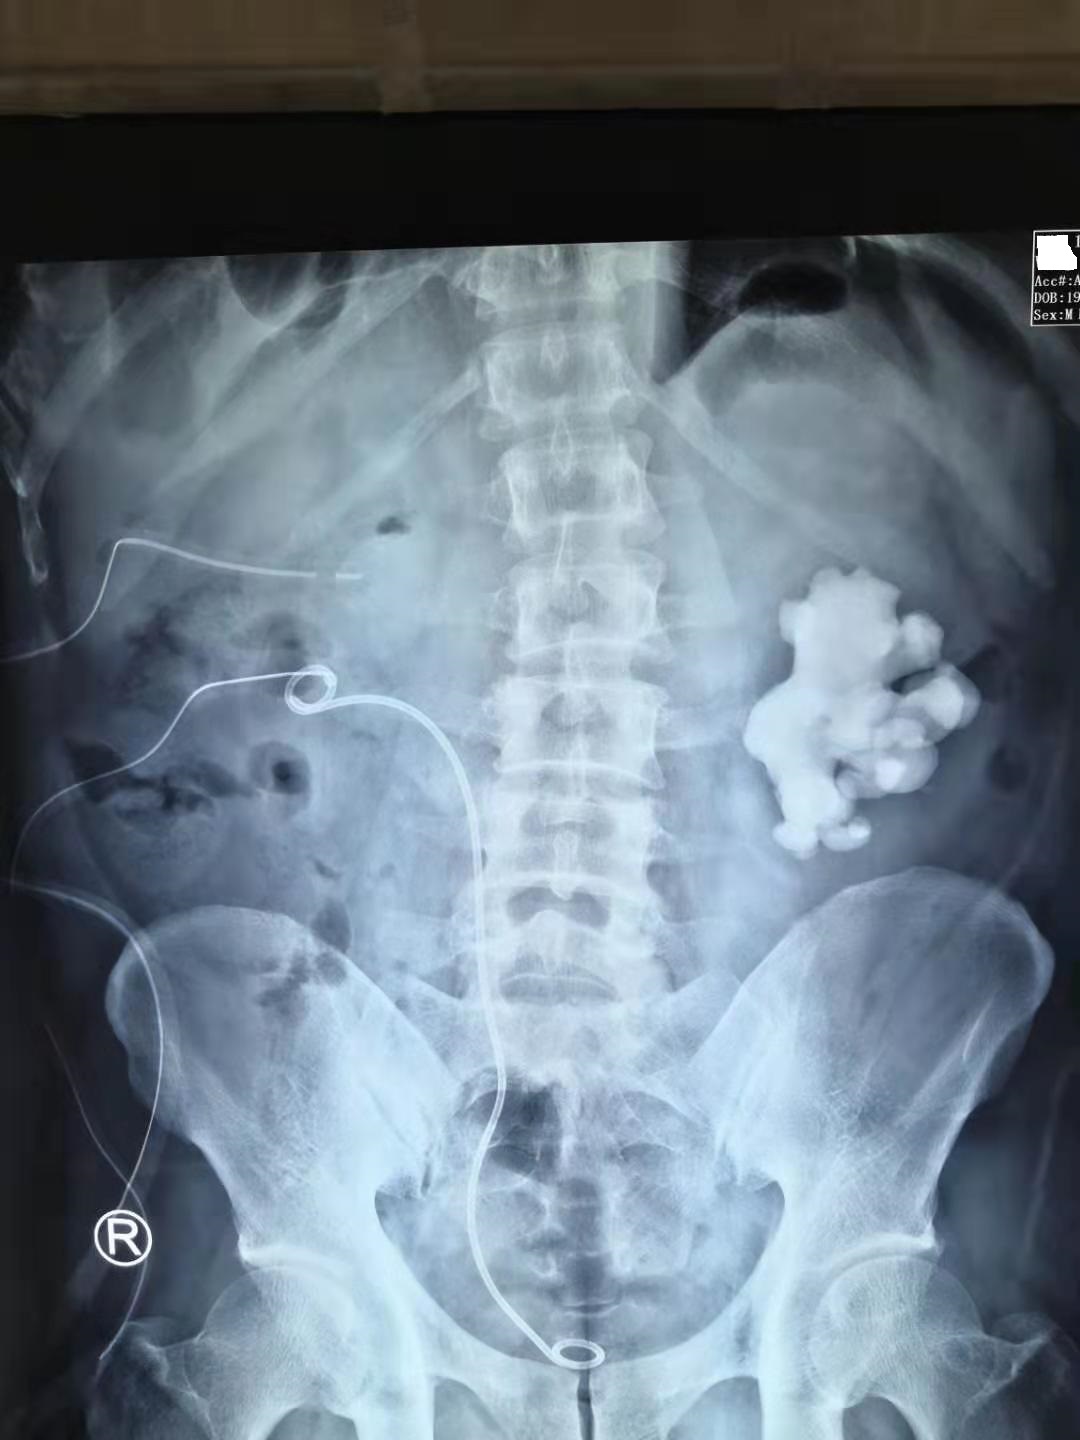

37岁的林先生是一名来自湖南的美团送餐员,由于"反复腰痛不适、下肢浮肿半年"来到我的门诊看病。经过泌尿系CT和腹部X线检查后,发现林先生的双侧肾脏集合系统长满了结石(双侧鹿角形结石),更要命的是,他的肾功能也处于尿毒症期的边缘。

林先生的双肾鹿角形结石